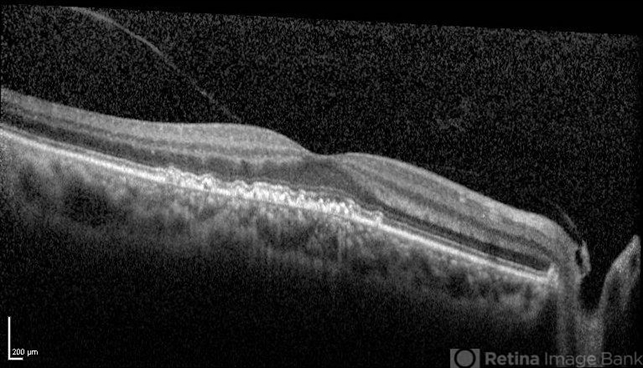

- cuticular drusen

- Cuticular drusen.